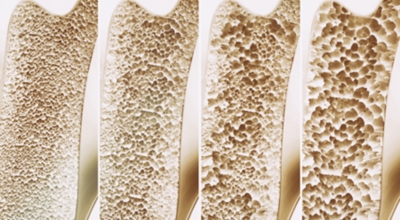

골다공증이란

골다공증이란 단단해야 할 뼈가 약해져서 부러지기 쉬운 상태가 되는 질환을 말해요. 골다공증이란 이름 그대로 약해진 뼈에 구멍이 송송 관찰되는 모습 때문에 지어진 명칭입니다. 나이가 들어가면서 관절이 약해지고 골다공증 으로 고생하게 돼요. 골다공증은 노화때문에만 발생되는 것이 아니랍니다.

작은 쇼크을 받아도 다치기 어렵지 않고 골절이 쉽게 오는 골다공증 증상은 과한 다이어트, 음주, 흡연, 규칙적이지 않은 식생활로 젊은분들에게도 골다공증이 많이 나타나고 있습니다. 여성의 경우, 폐경 후에 여성호르몬 분비가 다운되어 골밀도가 저하되므로 뼈가 스펀지처럼 되어 골절이 쉽게 오는 것으로 보입니다. 대퇴골, 손목 척추, 발목 부위에서 주로 골절이 발생하기 때문에 평소 골다공증에 좋은 음식 또는 스트레칭, 수영, 가벼운 산책 과 같은 저강도 운동을 하시는 게 좋겠네요.